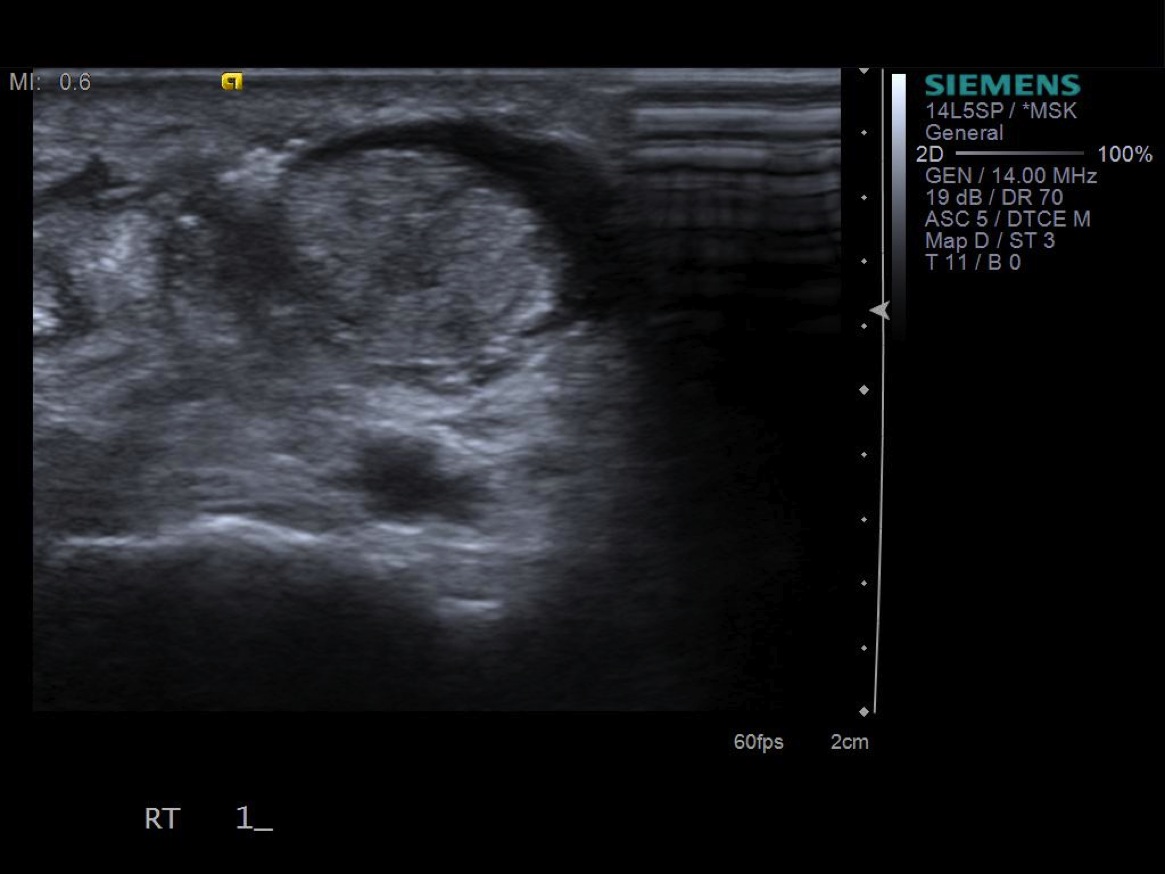

3. Place probe in short axis over first comparment extensor tendons-- Extensor pollicis brevis and abductor pollicis longus. description description

7. Under ultrasound guidance,advance needle into the 1st extensor tendon sheath. In this case the APL and EPB have separate sheaths and require their own injections. Test inject with 1% lidocaine. If no resistance, switch 1% lidocaine for injectable steroid mixture. If there is resistance, reposition needle and test inject again. Inject 1 cc of injectable steroid/anesthetic mixture.